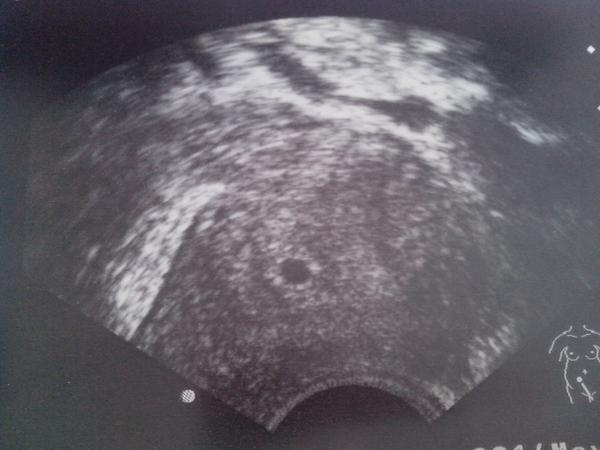

Ahoj holky moje.. no takze tehotna jsem, asi 5tt. Zatim je to tak mrnavoucke, ze to nemohl ani poradne zmerit. Nema uplne nejlepsi UZ. Srdicko jeste nemame, ale s tim sem pocitala, za 14 dni kontrola a snad uz tam bude tukat. No a mam zakaz romantiky 😀 krvaceni bylo z prekrveneho cipku, takze musime abstinovat.. prikladam fotecku a verte, ze za to stoji bojovat, i kdyz je to delsi doba.

@rybkaa dekuji.. ale opravdove gratulace az za 14 dni se srdickem.. pritel povidal, ze to vypada, jak pinpongovy micek 😀